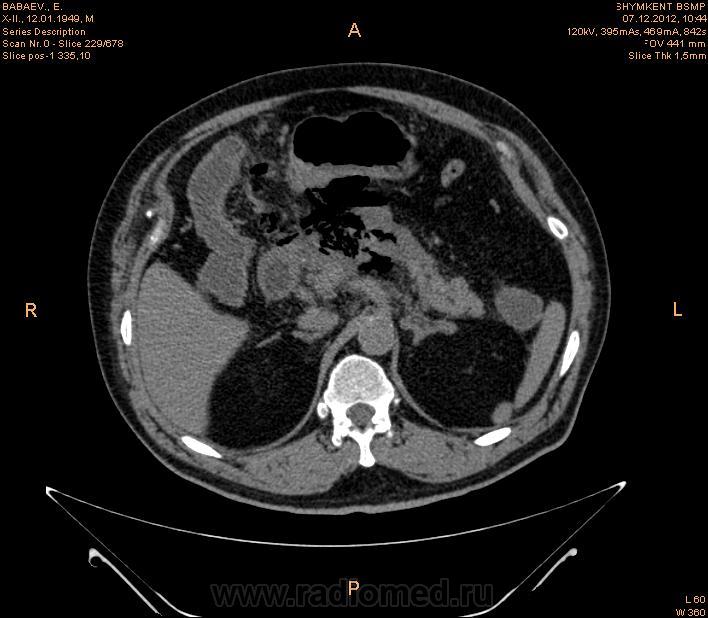

Здравствуйте , коллеги.Помогите пожалуйста разобраться.Больной мужчина 65 лет поступил с диагнозом Хр.панкреатит.Мех.желтуха. Эфгдс : Язва желудка.Хр.панкреатит. КТ - зак : Свободный газ в брюшной полости.Разрыв полого органа.Гиподенсные зоны с плотностью -827 ед.н., 937,0 ед.Н. Я оценила как свободный газ. На операций сказали Жировой панкренкроз. Больной умер.Неужели я ошиблось.

Если Вы имеете в виду гипозоны в проекции поджелудочной железы, то Вы ошиблись. Это редкий вариант панкреонекроза, эмфизематозный (острый некротический панкреатит)

Не очень редкий. Цитата: "Я оценила как свободный газ."  Как бы не видно "свободного" газа, он чем-то ограничен на всех срезах. Т.е. газовая дегенерация "чего-то", но не полого органа. Видимо в данном случае парапанкреатической клетчатки. При операции это никто из хирургов не видит, т.к. там есть и жидкость и кровь и только нами видимый газ.

поджелудочная диффузно увеличена ,в области тела определяется гиподенсивный относительно паренхимы поджелудочной железы  участок  с распространением в переднее параренальное пространство,преймущественно слева ,с включениями мелких пузырьков газа(инфицированный панкреонекроз),причем эпицентр имеет связь с вирсунговым протоком (разрыв ) с переходом процесса в брюшную полость.не исключал бы в данном случае и наличие желудочно-кишечного свища ,что может  иметь место  при таких изменениях.а так на первый план эмфизематозный(инфицированный панкреонекроз) острый панкреатит